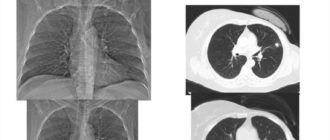

Возможно ли остановить развитие рака легкого 4 ст

Рак лёгких 4 стадии: сколько живут, симптомы перед смертью, методы лечения Рак лёгких является